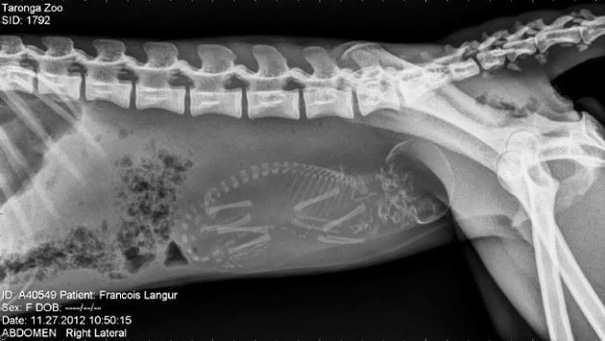

Unikāli rentgena attēli ar dzīvniekiem gaidībās

Bieži negadās publiski redzēt dzīvnieku rentgena uzņēmumus. Turklāt šie rentgena uzņēmumi ir veikti dzīvniekiem, kuri ir mazuļu gaidībās. Tagad ikvienam ir iespēja ielūkoties, kā dzīvnieku mazuļi attīstās savu mammu vēderos.